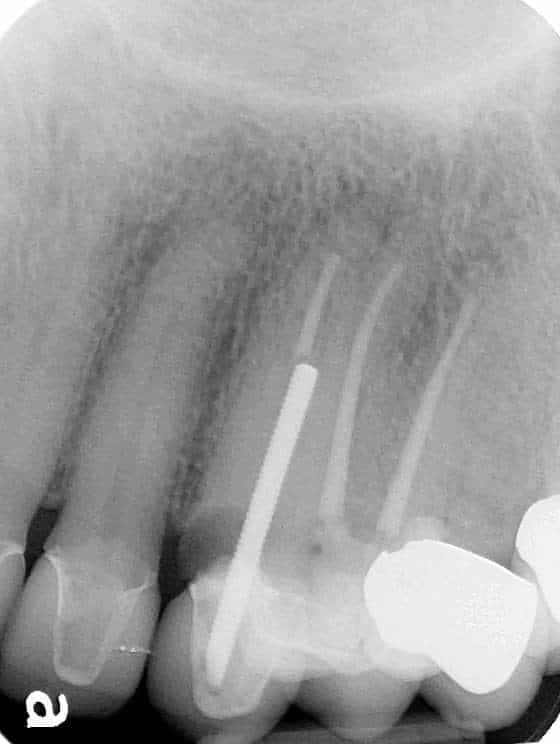

Below is a case of full arch same day temporization using the socket shield , root submergence and pontic shield techniques to preserve the site architecture . Neodent GM implants were placed in a guided fashion and same day temporization was performed using a milled PMMA.